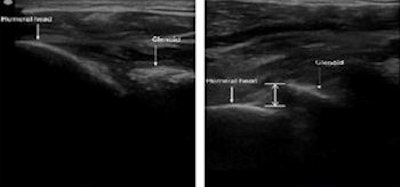

Ultrasound scans of normal (left) and anteriorly dislocated shoulder (right). The humeral head is located posterior to the glenoid rim in the normal shoulder. In the anterior dislocation, the humeral head is anterior to the glenoid rim.

After an ultrasound image of the humeral head and glenoid rim was obtained, the glenohumeral separation distance was determined. If ultrasound shows that humeral head placement is posterior to the glenoid rim, then there is no dislocation, according to Trinh.

Conversely, "if the humeral head placement is anterior to the glenoid rim, the shoulder is likely anteriorly dislocated," he said.